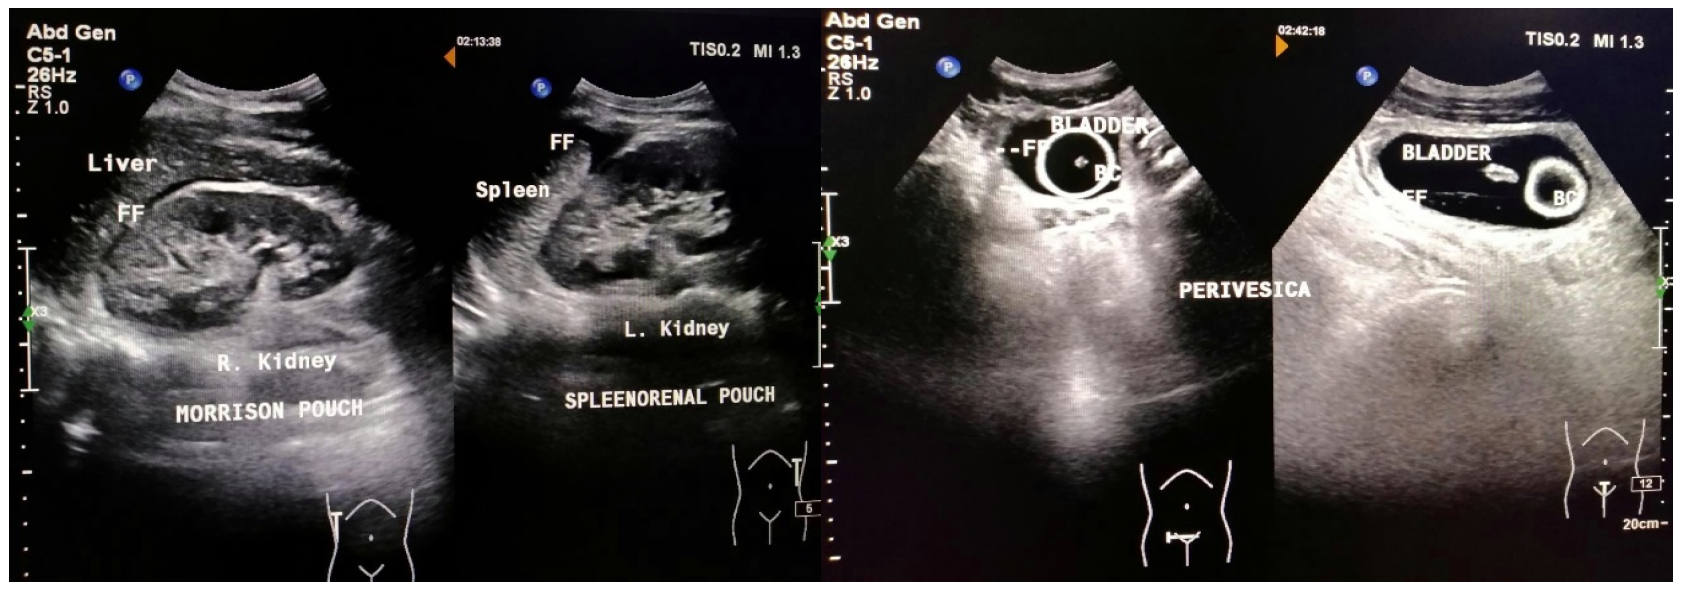

Child A, female, aged 12 years old. Twelve hours before admission to the hospital, when the patient was riding a motorcycle wearing a standard helmet, the patient had an accident colliding with another motorcycle from the opposite direction. The patient fell with her stomach hitting the road. After the incident, the patient was conscious, and the patient then complained of pain in the left side of the abdomen, headache (+), nausea (-), and vomiting (-). The rescuer took the patient to Ungaran General Hospital. The patient was infused, injected with painkillers, and treated for wounds. The family took the patient to Dr. Moewardi General Hospital Surakarta. The patient arrived at the emergency room six hours after the incident, and the pain was felt in the left abdomen. From the primary survey examination, the airway was still free with normal breathing, RR 20 x/m, no circulatory disturbances, BP 110/70 mmHg, HR 98 x/min with GCS E4V5M6, isochor pupil (3mm/3mm), pupillary light reflex (+/+), lateralization (-/-), and a temperature of 36.8 degrees Celsius. In the secondary survey, injuries were found in the left hypochondria region, no open wounds, no abdominal distension, bowel movements (+), and pain when palpated in the left upper quadrant of the abdomen. In stable hemodynamic conditions, the FAST examination was performed, and FAST (+) was obtained in Morrison's pouch and splenorenal (Figure 1).

Figure 1: FAST Examination (+) on the Morrison Pouch and Splenorenal Pouch

In this case, the patient showed FAST (+) in the Morison Pouch and minimal (+) in the Splenorenal Pouch. The FAST ultrasound results were then followed by a contrast CT scan of the abdomen, and spleen rupture grade IV and free intra-abdominal fluid were obtained. In this case, the result (+) in the Morison Pouch was not accompanied by liver rupture.